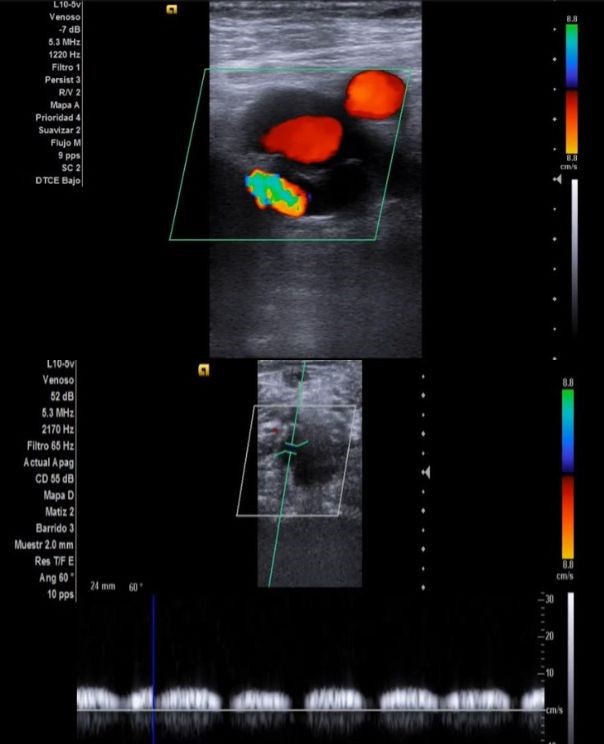

Ecografía venosa: venas femorales y poplíteas permeables. A nivel inguinal se observa imagen heterogénea, mal definida, sospechosa de malignidad.

Ecografía clínica urológica: se objetiva vejiga muy distendida hasta epigastrio con imagen heterogénea en pared posterior de vejiga de gran tamaño que capta al Doppler color sospechosa de malignidad. Con signo de hidronefrosis riñón izquierdo grado III.